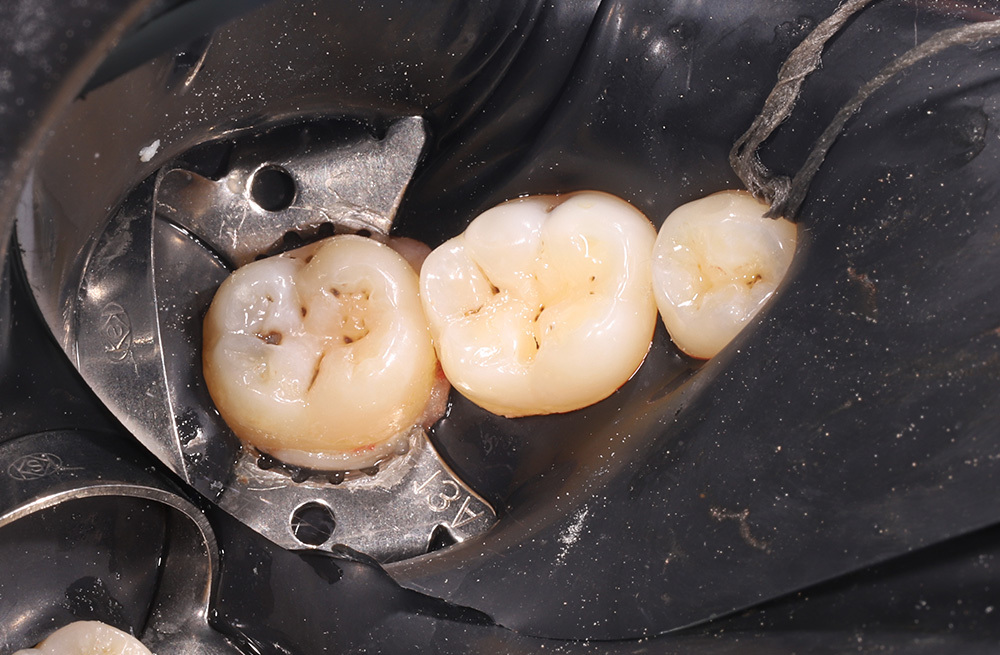

Композитная реставрация жевательных зубов при кариозном поражении